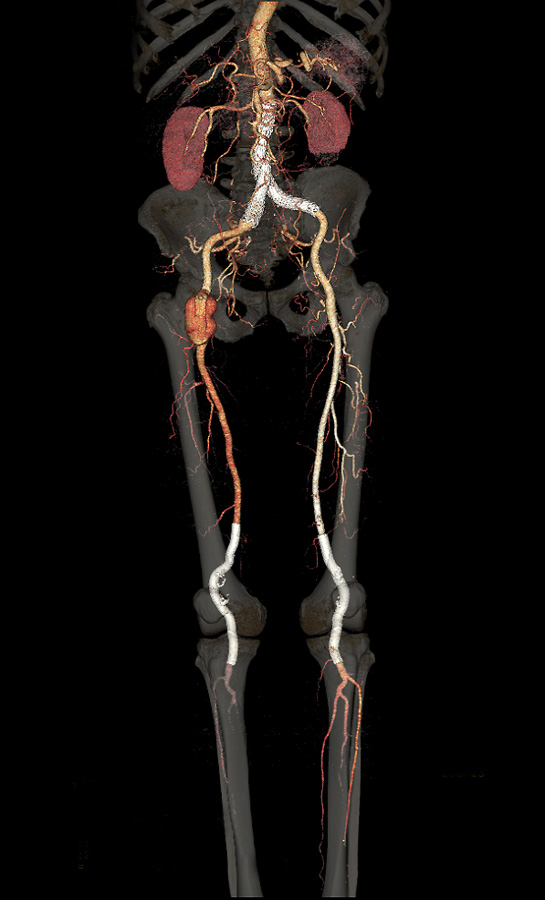

Endoprótese aorto-ilíaca + aneurisma femoral + endopróteses em poplíteas